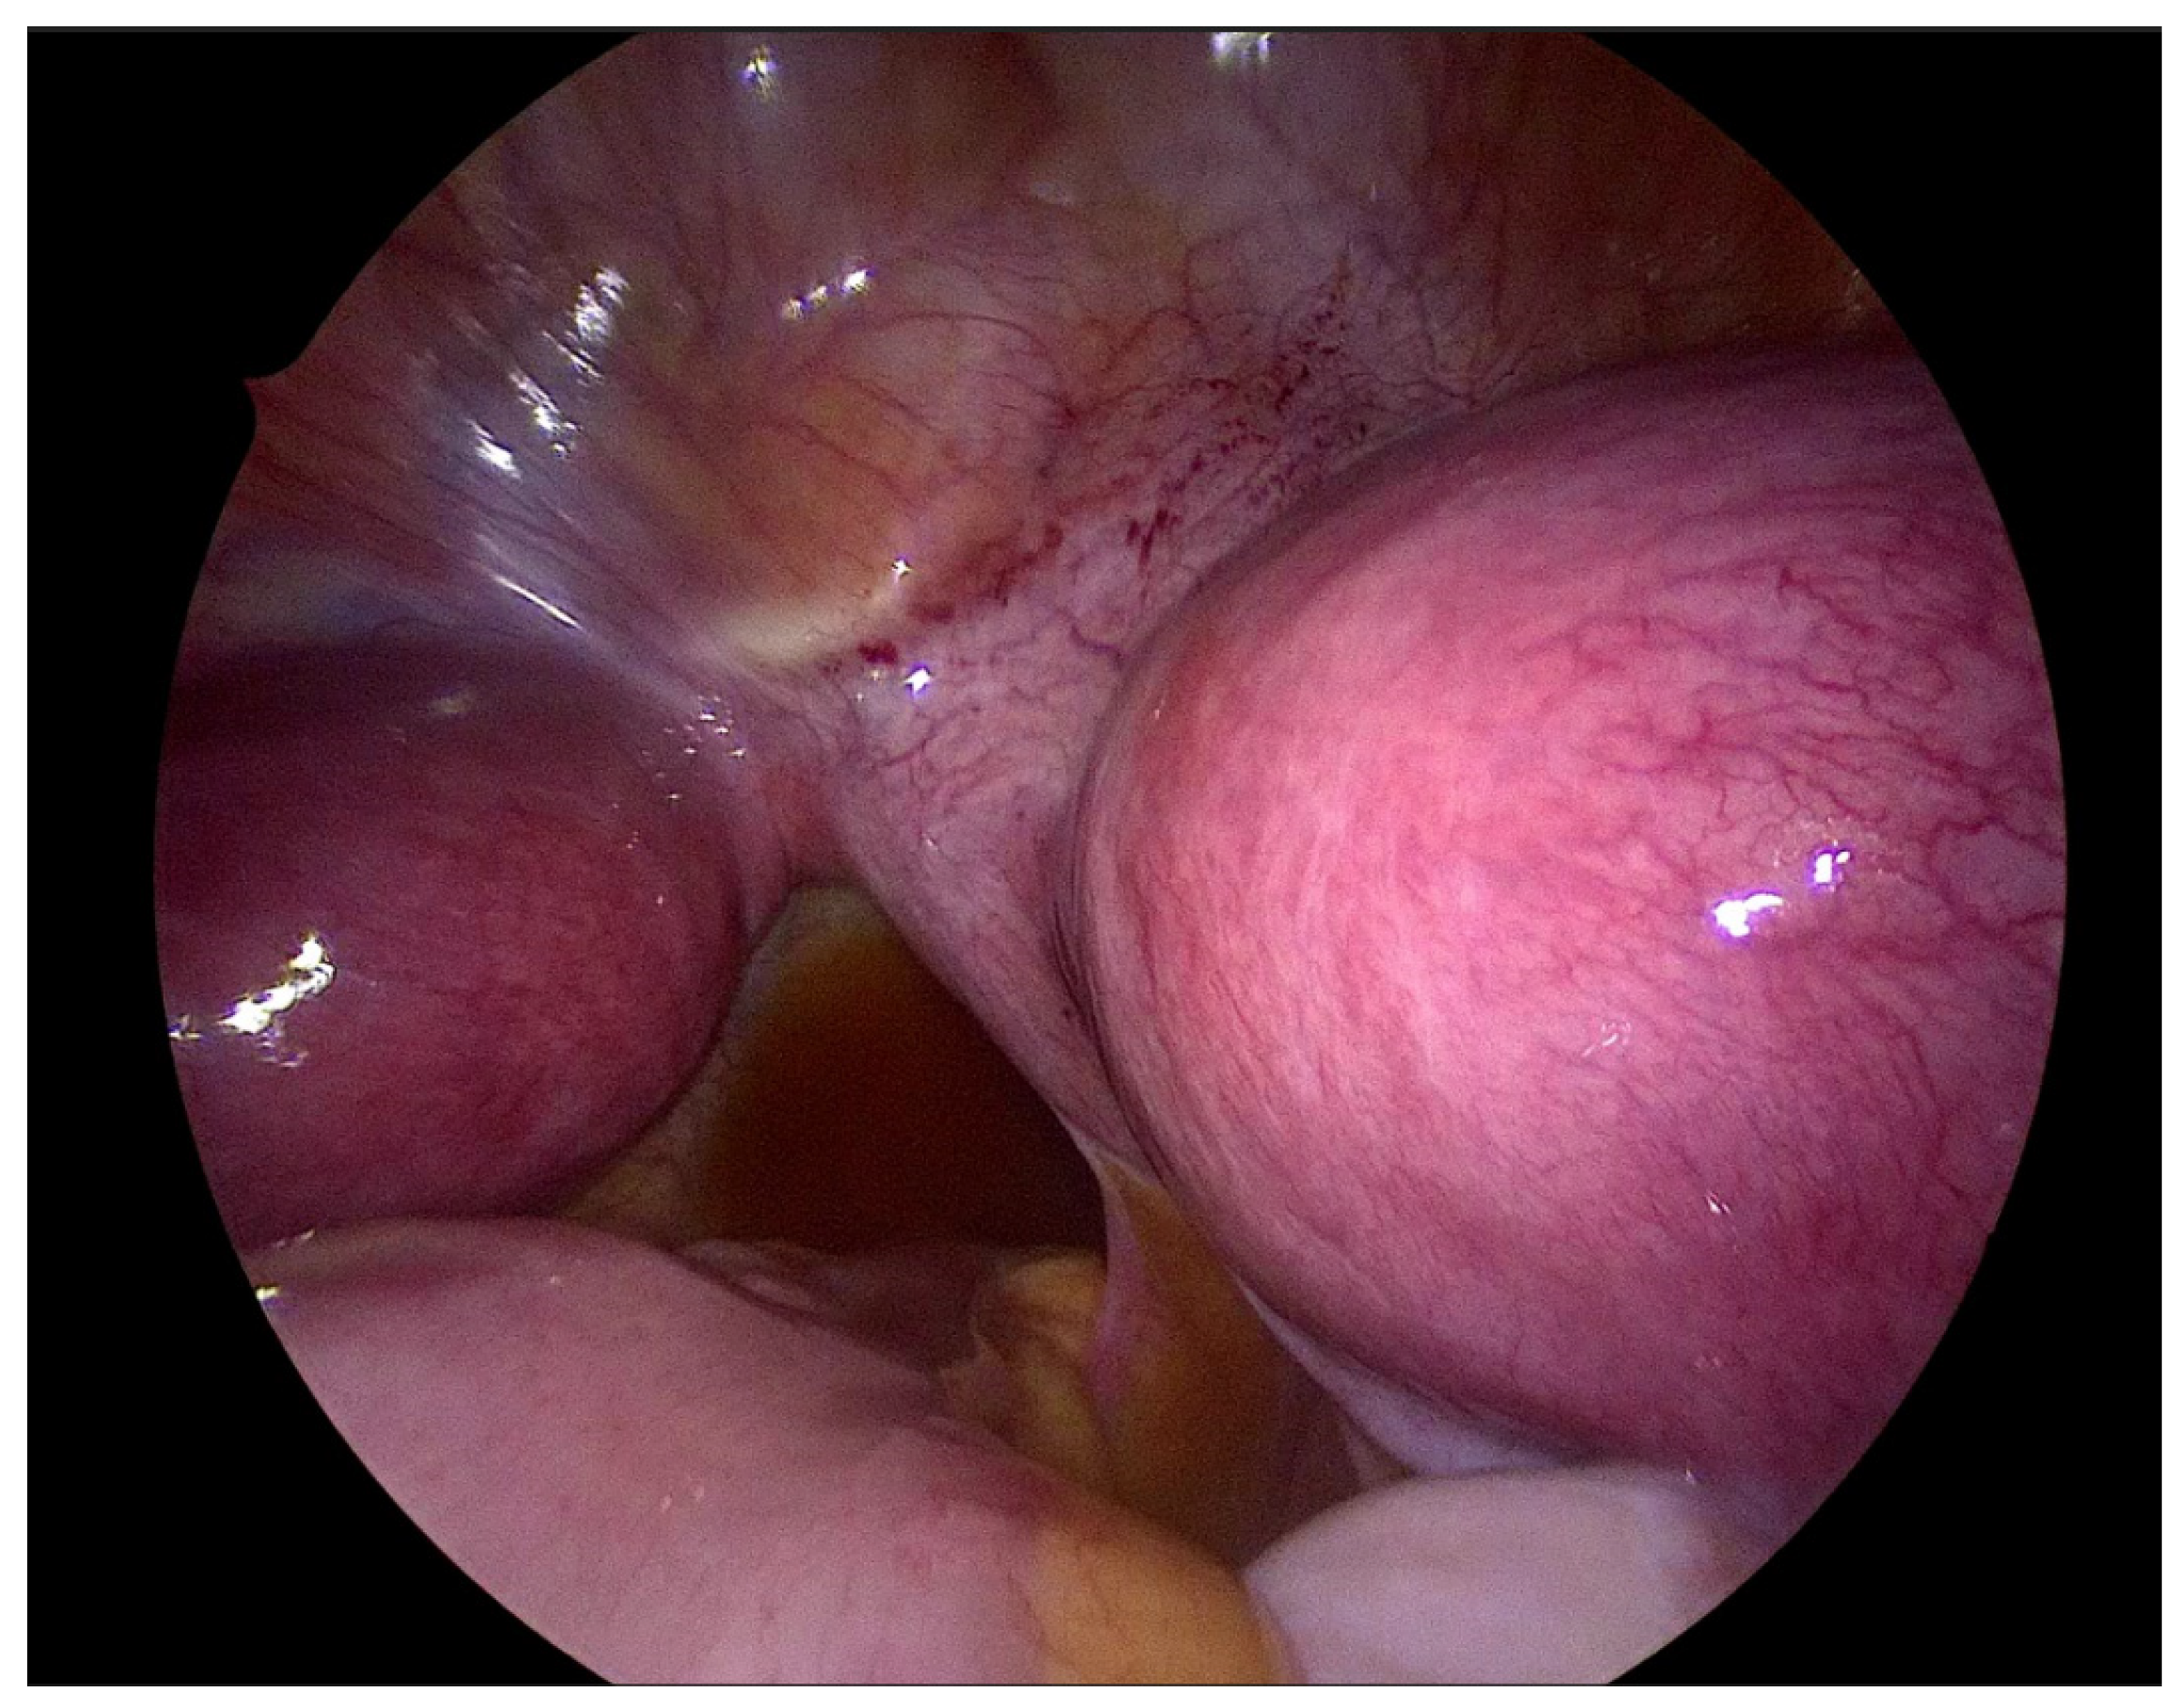

2.3. Surgical Technique

| Step 3. Surgical management Surgery is necessary when acute abdominal symptoms are present. “Wait and see” approach is only possible when the clinical situation allows it. Perform laparoscopy and vaginoscopy in order to achieve the correct diagnosis and treat concomitant hematosalpinx and endometriosis [14]. Intraoperative US is helpful to evaluate the place of resection. Unnecessary lengthening the time to diagnosis, contributes to unindentent consequence. |